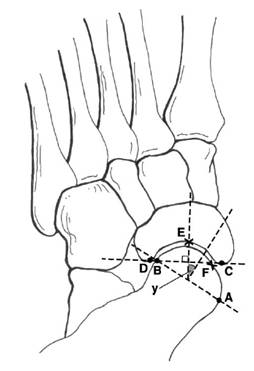

| 距舟覆盖角 1. 距骨关节面最内侧A,最外侧B,取两者连线 2. 舟骨关节面最内侧C,最外侧D,取两者连线 3. 两条直线垂线的夹角即为距舟覆盖角 – 正常人平均:10°(14°) – 扁平足平均:≥22

|